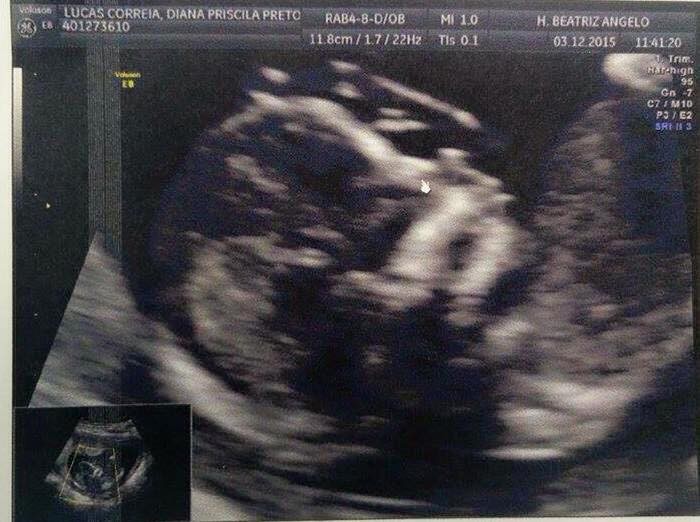

Depois de umas breves férias, os dois regressaram a Lisboa onde Ivo teve um presente de Natal antecipado como o próprio fez questão de anunciar nas redes sociais. O ator será tio no decorrer do próximo ano, pois a sua irmã, a cantora Diana Lucas, está grávida.

As felicitações rapidamente se multiplicaram e, embora ainda não se saiba o sexo do petiz, Diana garante que “é um bebé dificil”, na medida em que não deixou ver se se tratava de menino ou menina. “Mexia imenso as mãozinhas e perninhas, mas queria virar-se sempre para baixo”, escreveu a jovem num dos muitos comentários.